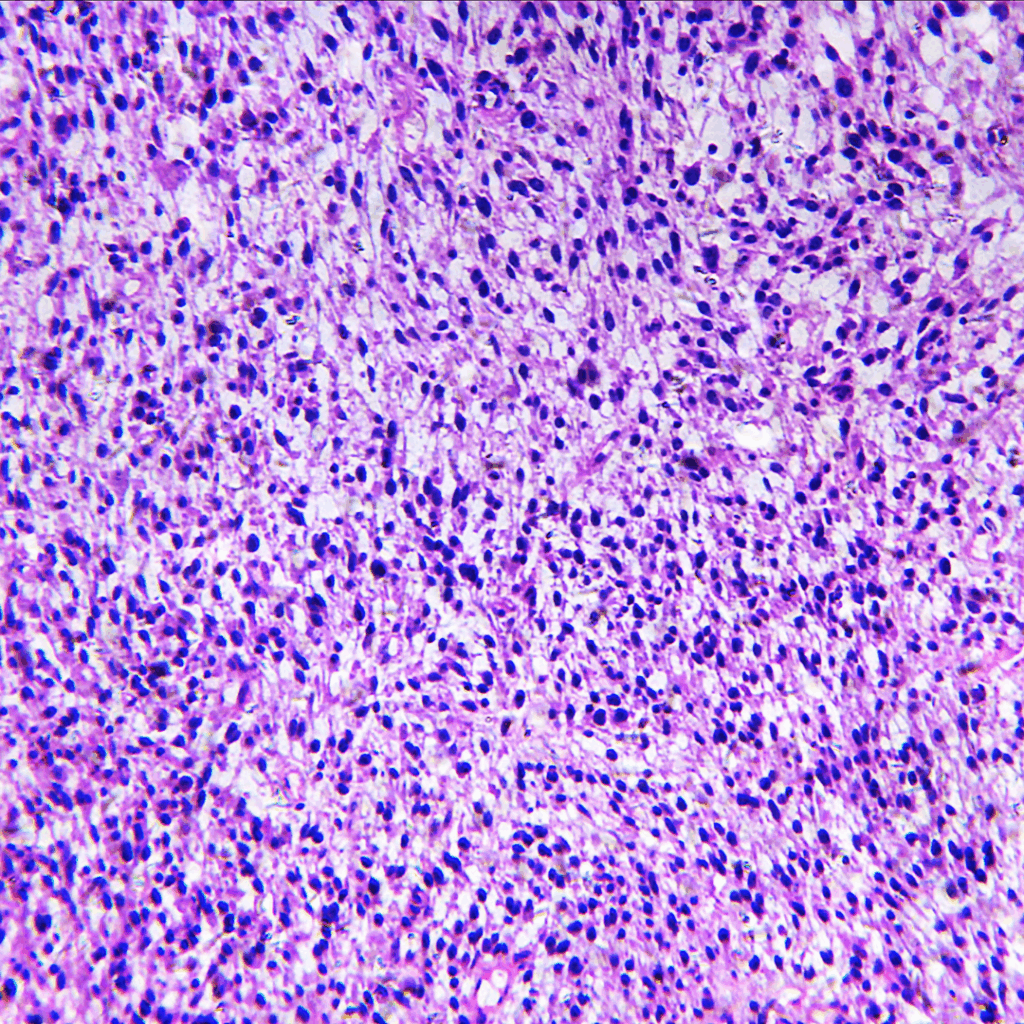

Rhabdomyosarcoma is one of a rare list of cancers. Only 700 people a year worldwide receive a diagnosis. They are mostly young youngsters or teenagers. Rhabdomyosarcomas fall into the following categories:

• Embryonal Rhabdomyosarcoma

• Botryoid Rhabdomyosarcoma

• Spindle Rhabdomyosarcoma

• Alveolar Rhabdomyosarcoma

• Pleomorphic and Undifferentiated Rhabdomyosarcoma